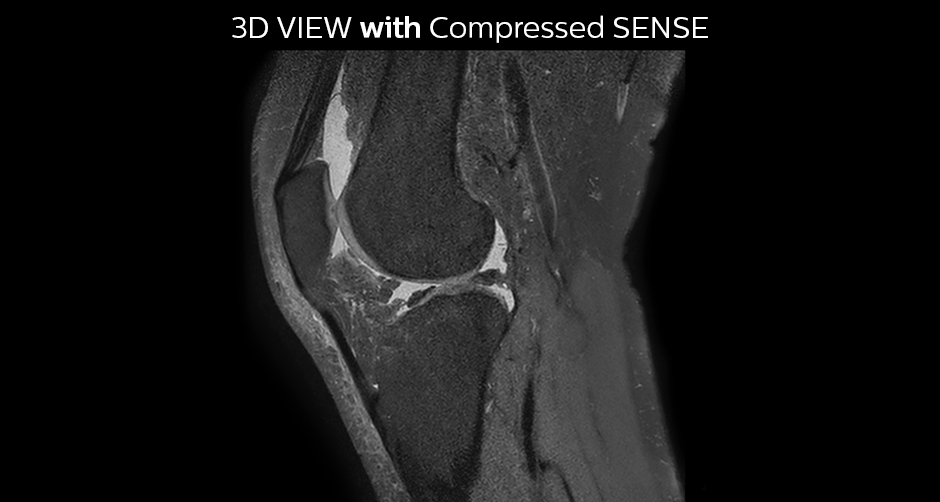

A good acquisition time with high resolution is obtained when moving from three 2D acquisitions in three planes to one 3D acquisition with Compressed SENSE. In this example, Compressed SENSE with 3D VIEW PD SPAIR is 50% faster than three separate 2D scans and has improved spatial resolution.

Without Compressed SENSE Scan time 2:55 + 3:37 + 3:51 = 10:23 min. Voxel size 0.55 x 0.65 x 3 mm

Three separate 2D PD scans in three orientations

With Compressed SENSE factor 10 Scan time 5:03 min. Voxel size 0.6 x 0.6 x 0.6 mm

3D VIEW PD SPAIR high resolution knee